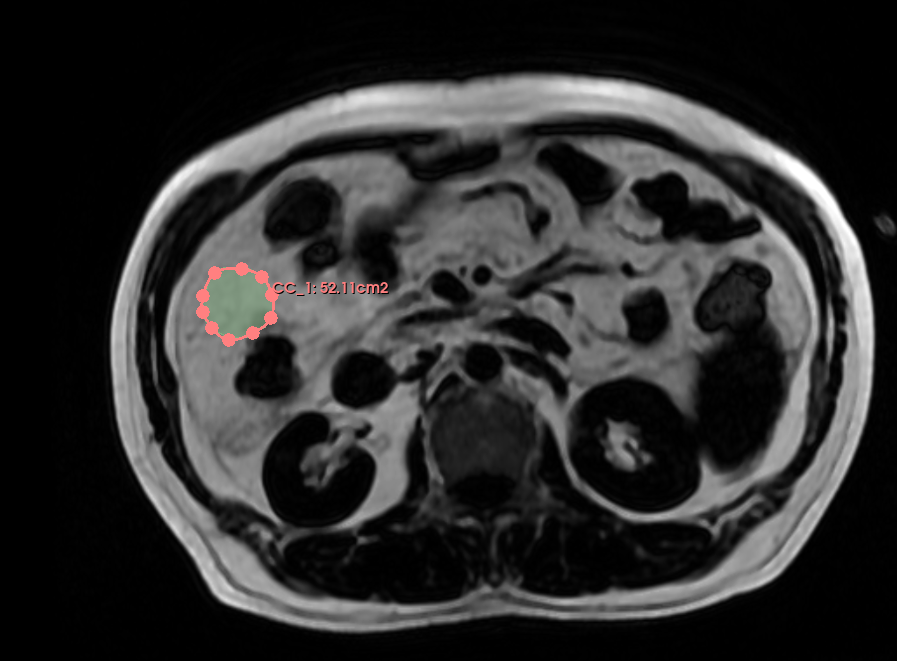

这个是我用闭合曲线之前画的面积